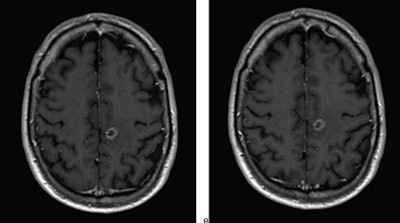

The study included 141 patients with known or suspected central nervous system conditions who underwent contrast-enhanced brain MRI with standard-dose gadoterate (0.1 mmol/kg); if a lesion was found, the patients underwent a second MRI with reduced-dose gadobutrol (0.075 mmol/kg) within 15 days.

"Comparison of reduced-dose gadobutrol and standard-dose gadoterate versus unenhanced imaging demonstrated noninferiority using 20% margin for three primary efficacy measures: subjective lesion enhancement, lesion border delineation, lesion internal morphology," the ARRS said.